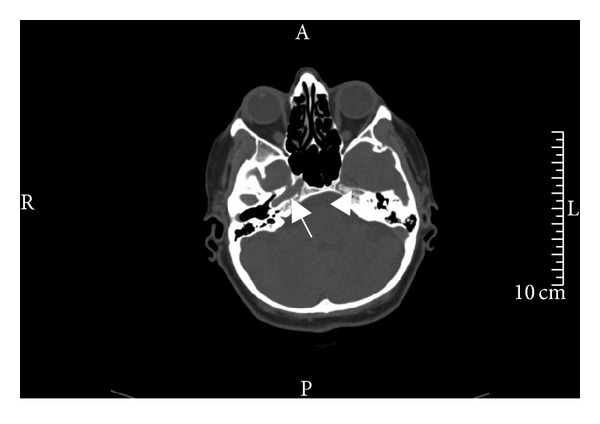

Figure 2.

This axial CT image of the cranial base shows that while the carotid canal in the petrosal bone is clearly visible on the right side (arrow), there is no visibility of a left carotid canal (arrow head).